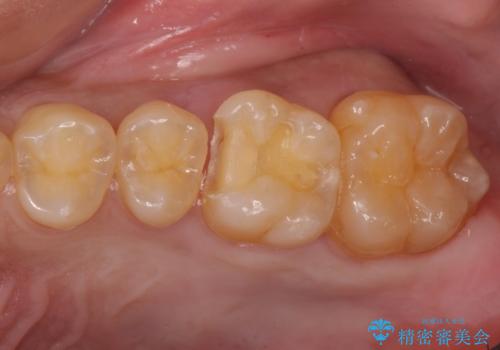

- 奥歯が虫歯になっていたため、セラミックインレーで修復しています。

治療前の写真では虫歯はわかりにくいですが、レントゲンではっきり見えます。

虫歯は外の入り口は小さいままで、中で広がっていることが多いため、要注意です。

口の中を目で見てわかるレベルの虫歯ですと、進行してしまっています。

虫歯はレントゲンを取らないと、発見できません。

歯科検診はあくまで余程の状態のスクリーニングですので、きちんとレントゲンを定期的にとって、早期に治療することが重要です。